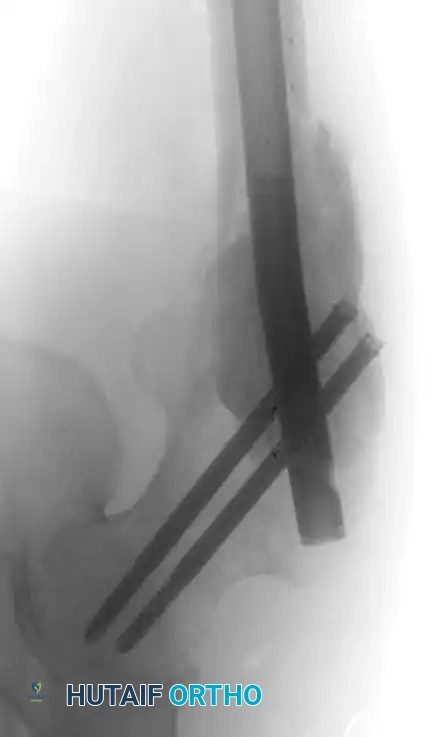

Fig. 22-20: (A) Impending pathological femoral fracture from metastatic squamous cell carcinoma. The femur fractured while the patient rolled in bed the night before scheduled prophylactic surgery. (B) Postoperative radiograph after fixation with a reconstruction nail and polymethylmethacrylate (PMMA) bone cement.